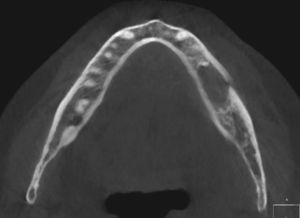

En la ortopantomografía de este paciente se observa una zona hipodensa localizada (aclaramiento) perirradicular en el diente 36 (fig. 1). La estructura mencionada abarca desde el ápice mesial del diente 37 hasta el ápice del diente 35. En la tomografía volumétrica dental adquirida consecutivamente, la masa hipodensa ocupante del espacio se extiende hacia caudal hasta el conducto mandibular del lado izquierdo y hacia bucal hasta el hueso compacto bucal (figs. 2 y 3). Este presenta dos perforaciones ovales a la altura del diente 36 (fig. 4). El techo del conducto mandibular del lado izquierdo no es apreciable en un tramo de aproximadamente 7mm. Se observan íntegramente las raíces de los dientes 35, 36 y 37.